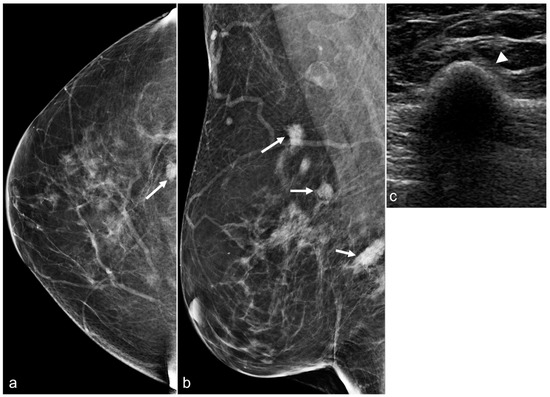

Figure 4. A 65-year-old woman with a history of subglandular silicone implants. Mammograms with magnified CC (a) and ML (b) views demonstrate calcified (arrows) and non-calcified fat necrosis in the left central breast. The patient underwent BES four years earlier.